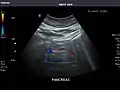

Gallbladder

Bile duct

Gallbladder: No stones, wall thickening, or pericholecystic fluid.

Common Bile Duct: Nondilated measuring 1.3 mm at the level of the porta hepatis.